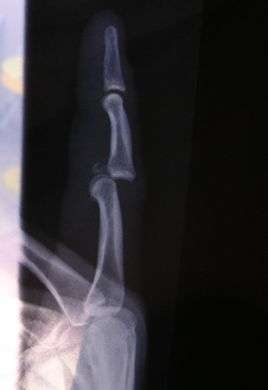

Dislocation of the left index finger

Radiograph of right fifth phalanx bone dislocation- Radiograph of left index finger dislocation

X-rays are usually taken to confirm a diagnosis and detect any fractures which may also have occurred at the time of dislocation. A dislocation is easily seen on an X-ray.[8]